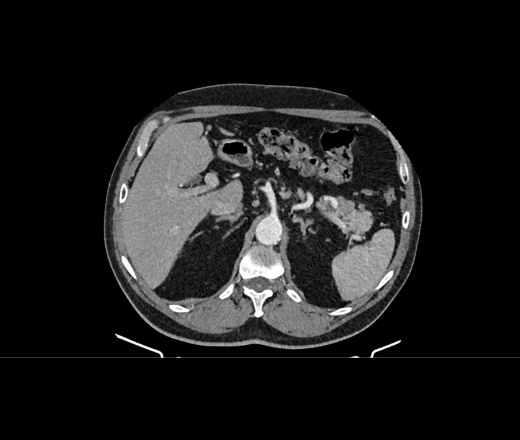

Здравствуйте, подскажите пациент 60 лет, особо жалоб нет, на узи было изменения в печени, в хвосте поджелудочной железы отмечаются немного гиподенсивные изменения может ли это быть раком? на МРТ лучше покажет?

В печени гиперваскулярное образование в 5 сугменте, требует наблюдения. Поджелудочная - ничего плохого не вижу. А вот лимфоаденопатия выражена. Если мтс, то откуда - не знаю